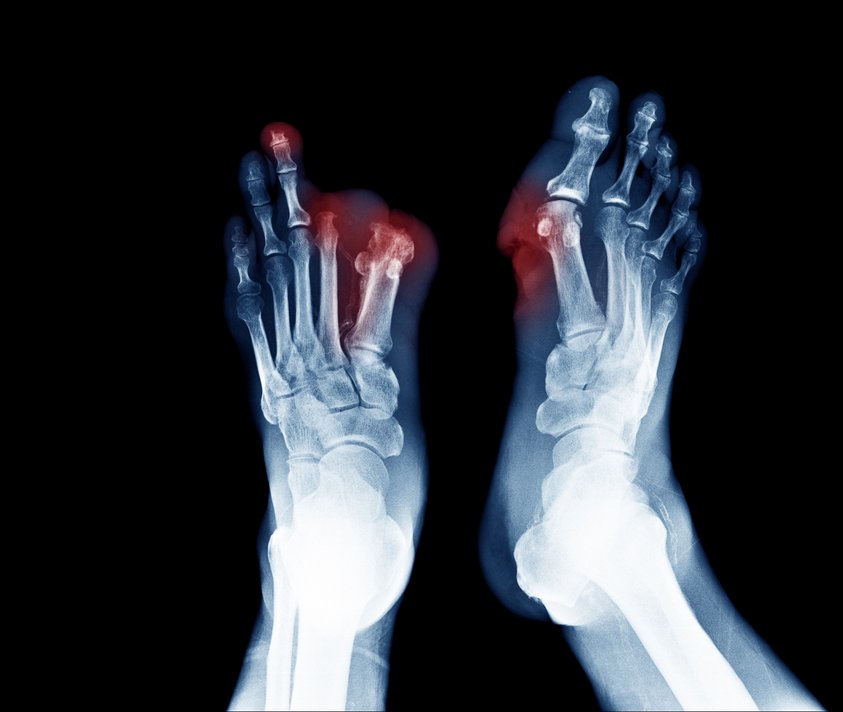

„Je eher Patienten mit Schmerzen im Bein oder Fuß, Verfärbungen der Haut oder offenen Wunden an den Beinen zum Gefäßspezialisten gehen, umso besser ist die Chance, dass ein Absterben der Gliedmaßen und somit eine Amputation verhindert werden kann“, so Lichtenberg.

Jedes Jahr müssen in Deutschland rund 60.000 Zehen, Füße oder sogar Beine amputiert werden. Bei rechtzeitiger Behandlung könnte dies verhindert werden!